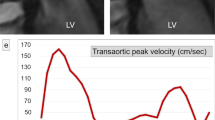

Peak mitral inflow velocity tracking on MASS using 4D flow CMR. The software automatically computes in-plane velocity maps within the contoured area for the complete cardiac cycle. Automated analysis of the LV volumes from short-axis cine stack of images using standard methods of endocardial and epicardial contours (a). Three-dimensional multi-planar reformatted plane showing the LV geometry in 3D (b). Short-axis cine stack view and three-directional blood flow images showing mitral inflow as color-coded velocity maps on 4D flow CMR during diastole (c, d). Peak mitral inflow velocity trace demonstrating peak E-wave and peak A-wave velocities (e)

The software automatically computed in-plane velocity maps within the contoured area of mitral inflow and identified the peak velocity with the streamlines for the complete cardiac cycle.

Finally, peak E-wave and peak A-wave velocities were recorded from the maximum velocity graph generated by the software. Only the peak E-wave velocity was recorded for atrial fibrillation (AF) patients.